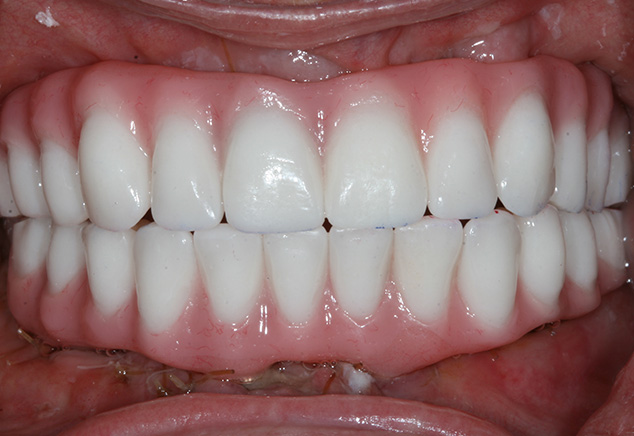

At the insertion appointment, the healing caps were removed and cleaned with Chlorhexidine. Figure 15 demonstrates the excellent healing of the soft tissue prior to insertion of the prosthesis. Once inserted, the esthetics, phonetics, and OVD of the prosthesis were confirmed. The occlusion was adjusted as needed. Screws were tightened to 15 Ncm, screw access openings were filled with Teflon tape to within 2mm of the surface, and a soft material such as Telio or Fermit was used to seal the access. A maxillary acrylic nightguard was fabricated to aid in protection of the occlusal surfaces from wear and to help reduce any parafunctional habits. The completed case is shown (Fig 15, Fig 16, Fig 17, Fig 18). At subsequent appointments, the prostheses were evaluated to determine if they needed to be removed to assess the soft tissue or if any contouring of the acrylic was necessary. Eventually the soft material used to close the access can be replaced with a hard composite material.